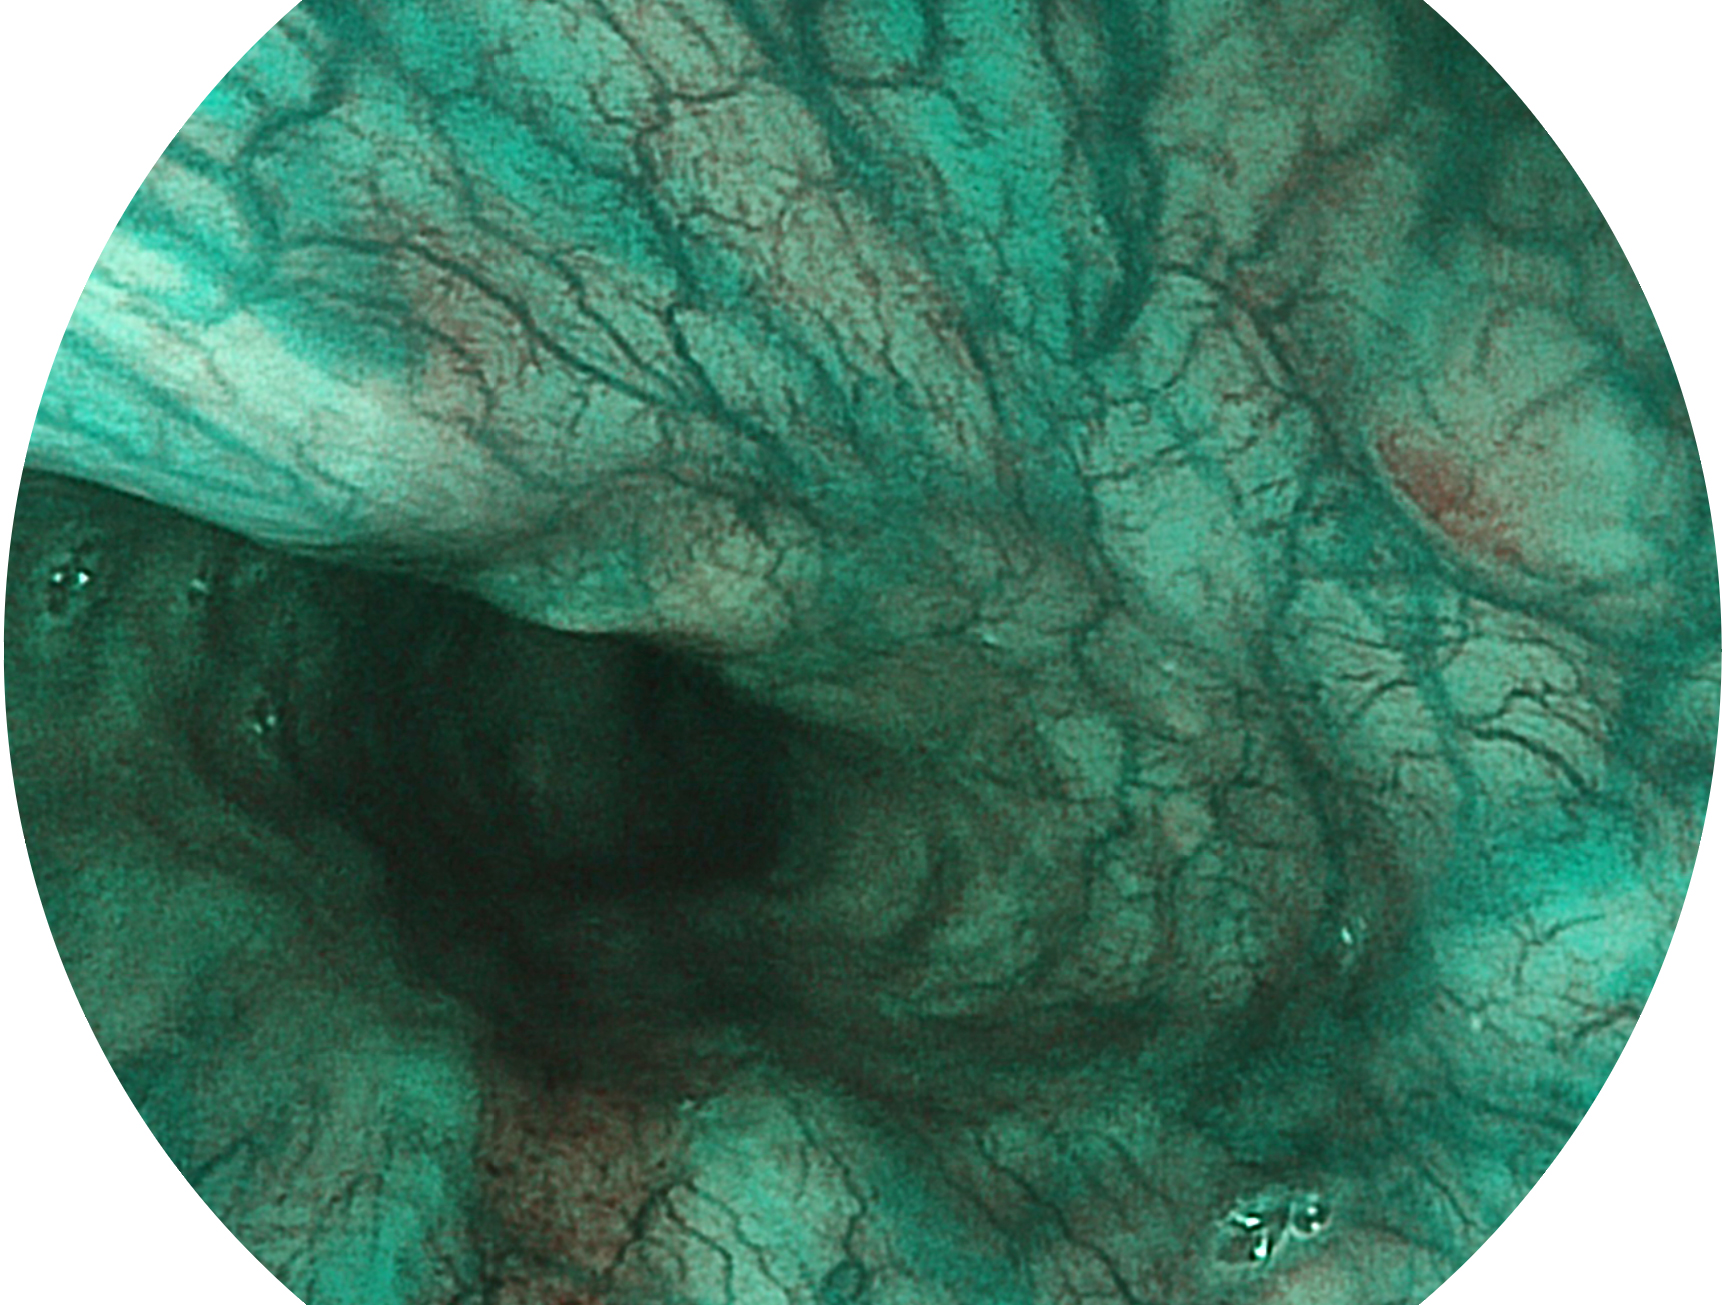

银河优越会新开发的内镜染色技术,主要是基于多波长LED 光源的开发,VLS-55Q 四波长LED 光源是由四个不同颜色的LED光按照相应照明模式所规定的特定发光比例进行合束后形成,合束后形成的照明光的光谱由红光、绿光、蓝光及蓝紫光这四个不同的波段范围构成。具有更高光谱自由度,通过光谱比例的控制,实现了聚谱成像技术,英文全称为“Spectral Focused Imaging, SFI”,缩写为“SFI”和光电复合染色成像技术,英文全称为“Versatile Intelligent Staining Technology, VIST”,缩写为“VIST”。